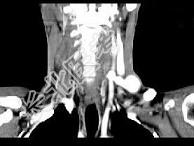

- 单项选择题男,46岁, 外伤后左下颈搏动性肿块,CT如图所示, 最可能的诊断是 ( )

A、左颈部血管瘤

B、左颈动脉体瘤

C、左颈静脉球瘤

D、左颈总动脉假性动脉瘤

E、左颈部动静脉畸形